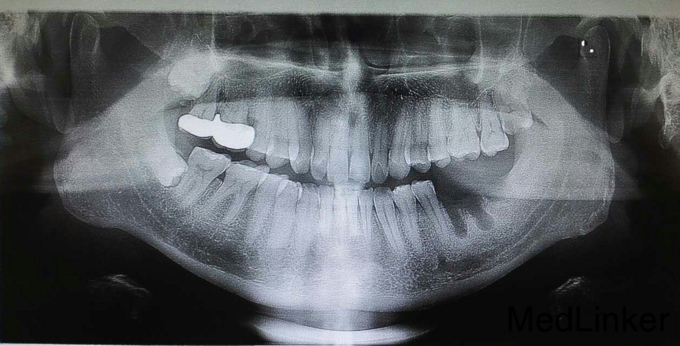

患者男39岁 后牙缺失 欲种植

后牙缺失 欲种植